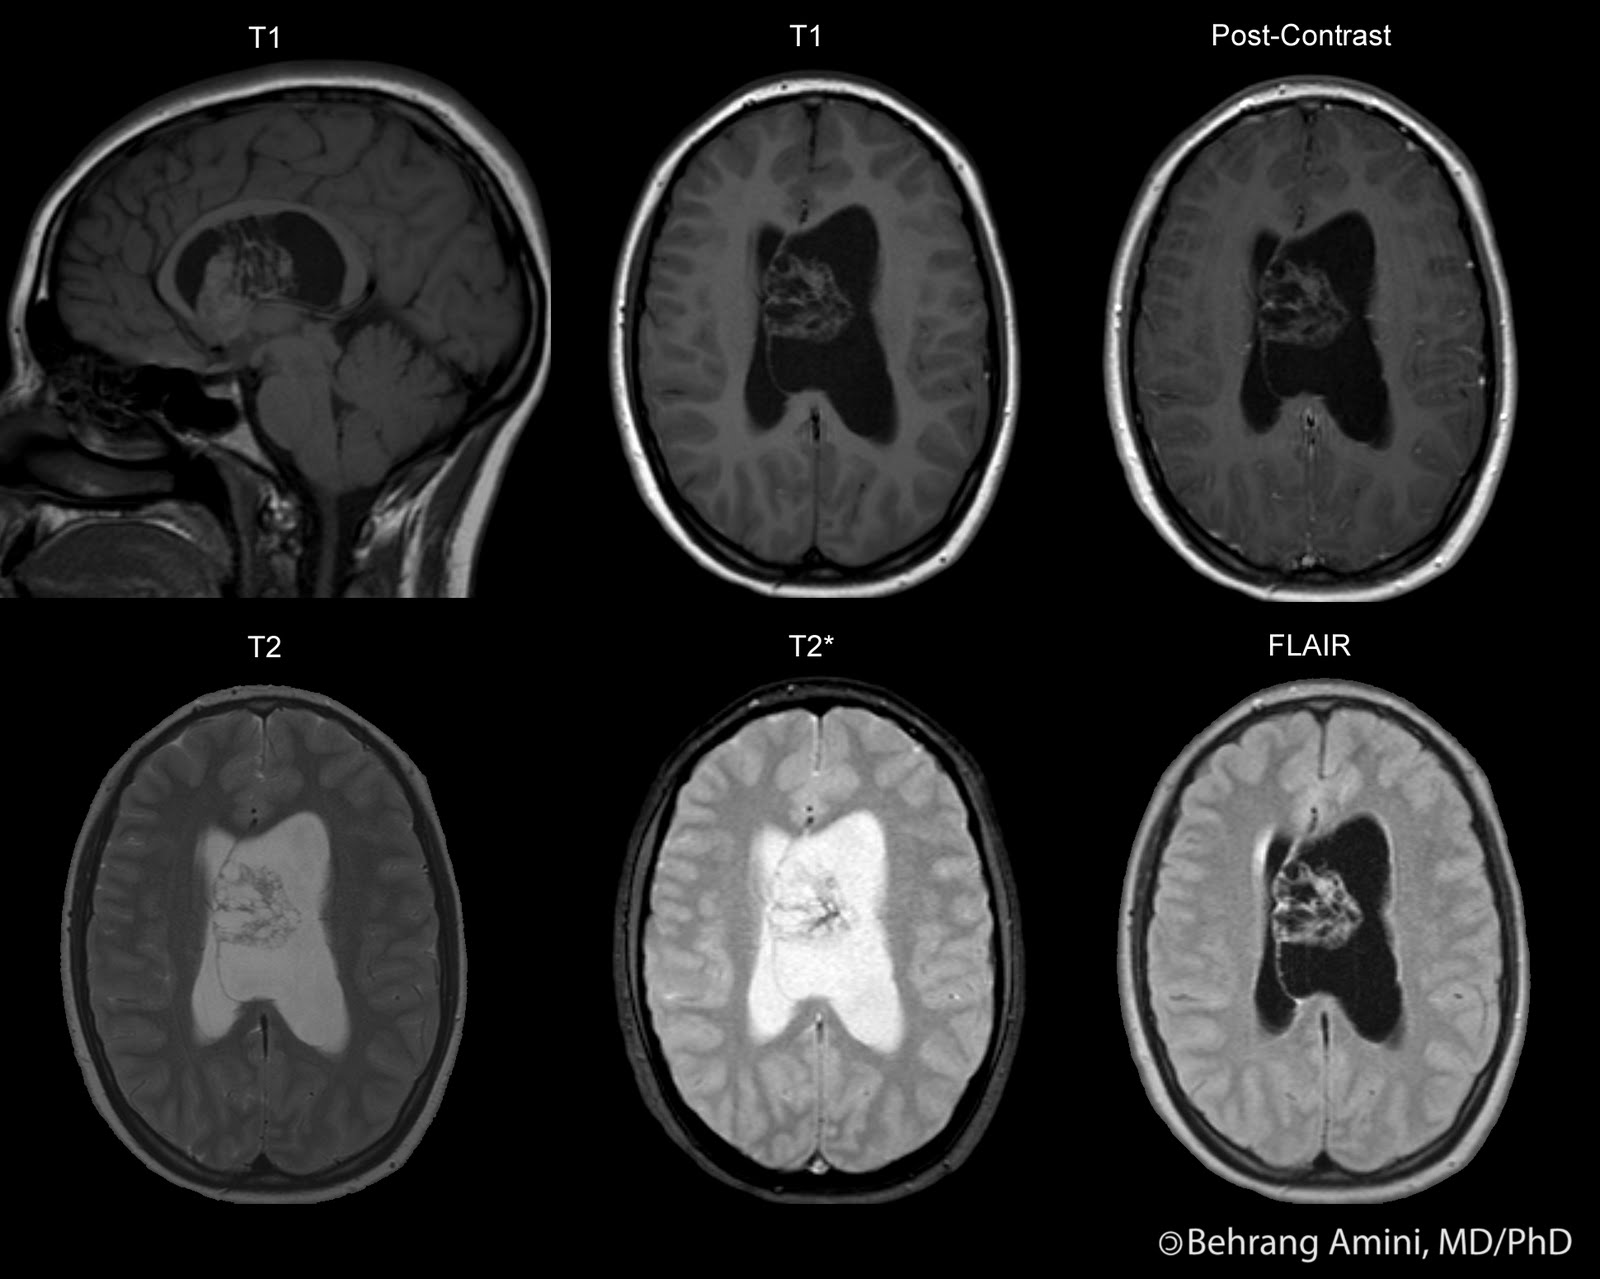

Roentgen Ray Reader Central Neurocytoma

Roentgen Ray Reader Central Neurocytoma What Is Central Neurocytoma Central neurocytomas are generally noncancerous (benign) brain tumors in the ventricles,. central neurocytomas are who grade 2 neuroepithelial intraventricular tumors with fairly characteristic imaging. what is central neurocytoma? central neurocytoma (cn) is a benign primary neuronal tumor of the central nervous system (cns) most often found in. central neurocytoma is a very rare brain tumor of. What Is Central Neurocytoma.